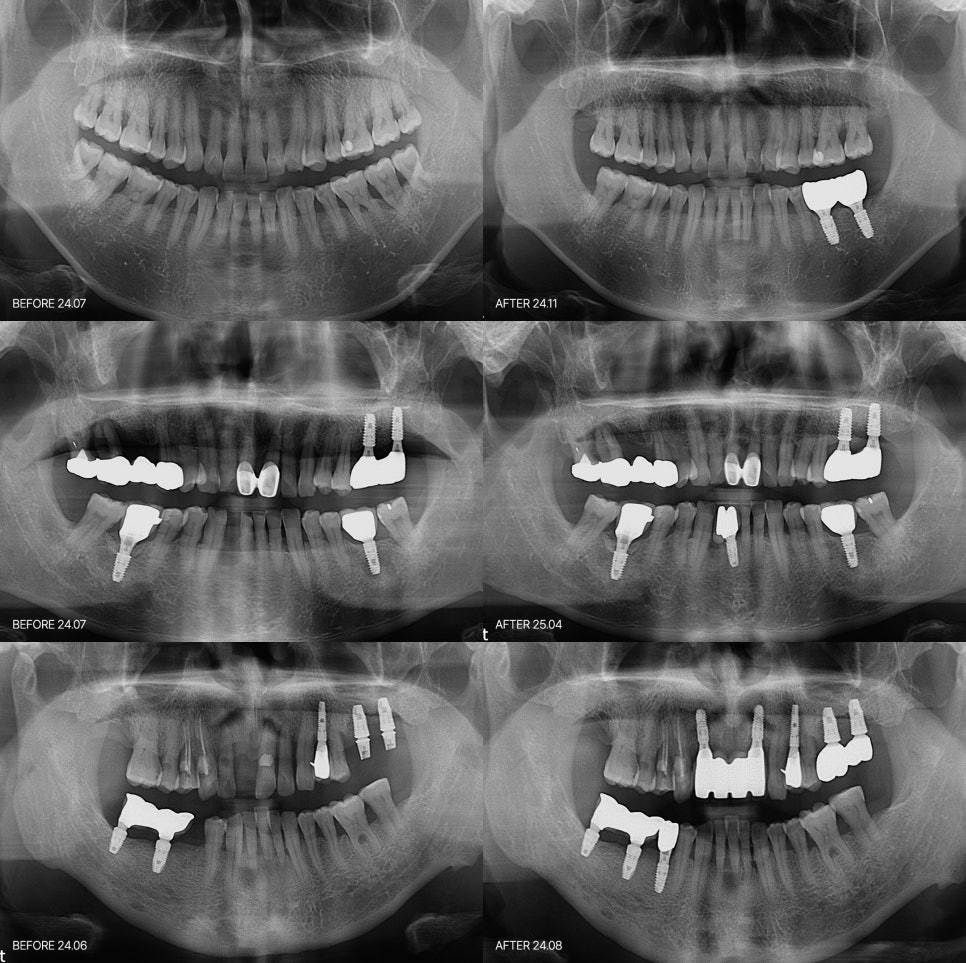

임플란트의 붓기 통증 잇몸에서 시작되는 신호일 수 있습니다

이 정도는 붓기 통증은 정상이라고 할 수 있을까요 임플란트 치료 후에 가장 많이 듣는 상담 전화들이 "생각보다 많이 부은거같은데 많이 아픈거 같은데 저 괜찮은 거 맞나요?" 라는 말들을 많이 하세요. 수술 직후에 약간의 불편감은 있을거라는 인지는 가지고 계시기에 처음에는 크게 걱정을 하지는 않으십니다. 하지만 몇일이...